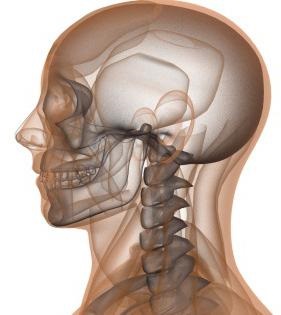

nyakszirti közös

Koponya, anatómia, amely lehetővé teszi neki, hogy készítsen elsősorban a védelmi funkció, akkor is végezze el a különböző mozgásokat, köszönhetően a közös összekötő nyakszirtcsontba és az első csigolya (atlasz). A mellékhatások együttes alkotja a nyakszirti ízfelszínekkel; ez egy pár (mert a két csatlakozik a condylus izületi fossae Atlas) ellipszoid, a membrán két (első és hátsó) és oldalsó szalagok.

A halántékcsont a koponya egy bonyolult szerkezetű, valójában ez hallási mozgást csatornát. Ez három részből áll, amelyek a perinatális időszakban és a születés után képviselik a különböző csontok, végül egyesülő egyetlen. Így, három részből áll: pikkelyes, és köves dobrész, elválasztva, közbenső varratok.

Pikkelyes rész tartalmazza a járomcsonti folyamat kialakításában játszik szerepet a közös. Ezért az a tárgyalás során megkezdődik, ami bemegy a timpanon (lokalizáció a középfül), ahol a hallás ossicles: a kalapács, az üllő és a kengyel, valamint egy kis lencsés hryaschik közöttük. Ezek az elemek is részt vesznek a felvétel a hanghullámok áthaladó őket rezgéseket a belső fül.

Rocky bone nagyon erős, és az a szerepe egy csontváz hallás és az egyensúly. A dobüreg bonyolult csontváz rendszer, amely egyfajta labirintus, ami alapján a belső fülbe. Továbbá, itt van egy rendszer, lyukak és csatornák vezető idegrostok és hajók.

Tehát, köszönhetően a kifinomult eszközök, halántékcsontba a koponya több funkciót végez.